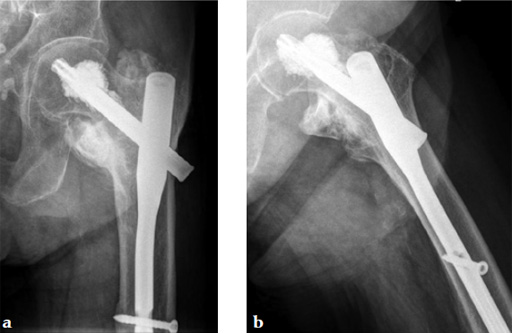

An 82-year-old woman with an unstable pertrochanteric fracture of the right proximal femur. Her Barthel Index was 80 and her preoperative Parker mobility score was 5, which means that she was walking at home unassisted. The patient's preoperative Parker mobility score of 5 was reached again at the 3-month follow-up.